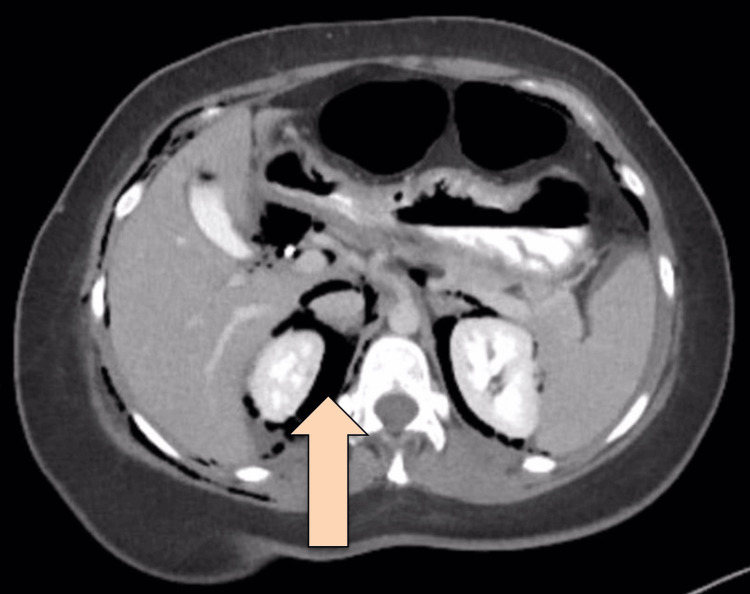

CT abdomen with IV and oral contrast post-ERCP showed pneumobilia with evidence of stent in the biliary system seen in a satisfactory position, significant pneumoretroperitoneam, small amount of retroperitoneal leaked contrast inferior to the second part of the duodenum, bulky and edematous pancreatic head, and uncinate process suggestive of acute pancreatitis, no intra-abdominal collection, and minimal amount of free fluids. There was extensive soft tissue emphysema along the anterior neck, lateral chest, and abdominal wall, severe pneumomediastinum, and minimal bilateral pneumothoraxes, with a chest tube seen on the right side in a satisfactory position, and a tiny area of contrast leakage was seen in the right posterior-lateral of the mid esophagus at T6 (Figures 2–4). The impression was double perforation at the second part of the duodenum and esophagus.

Since the patient was still tachycardic and still had leukocytosis, interventional radiology (IR) was consulted on upsizing the collection drainage to 12 French catheters. Drain output was around 100-150 ml/24 hours, billous, and started to be mixed with pus. Follow-up CT showed persistent communication of the retroperitoneal paraduodenal collection with the posterior aspect of the most distal part of the CBD. The oral contrast flow through the entire GI tract showed no evidence of a leak. Interval change in the position of the iliac fossa drain was observed, with its tip seen within the upper aspect of the right iliac fossa collection. A reduction in the size of the multi-loculated retroperitoneal collections was noted. The largest locule is seen in the right iliac fossa, which measures 9 x 4 x 12.8 cm, compared to 10 x 5 x 15 cm. Another locule was seen posterior to the duodenum, measuring 3.6 x 2.7 x 9.4 cm compared to 4.3 x 5.8 x 11 cm (Figures 6–7).